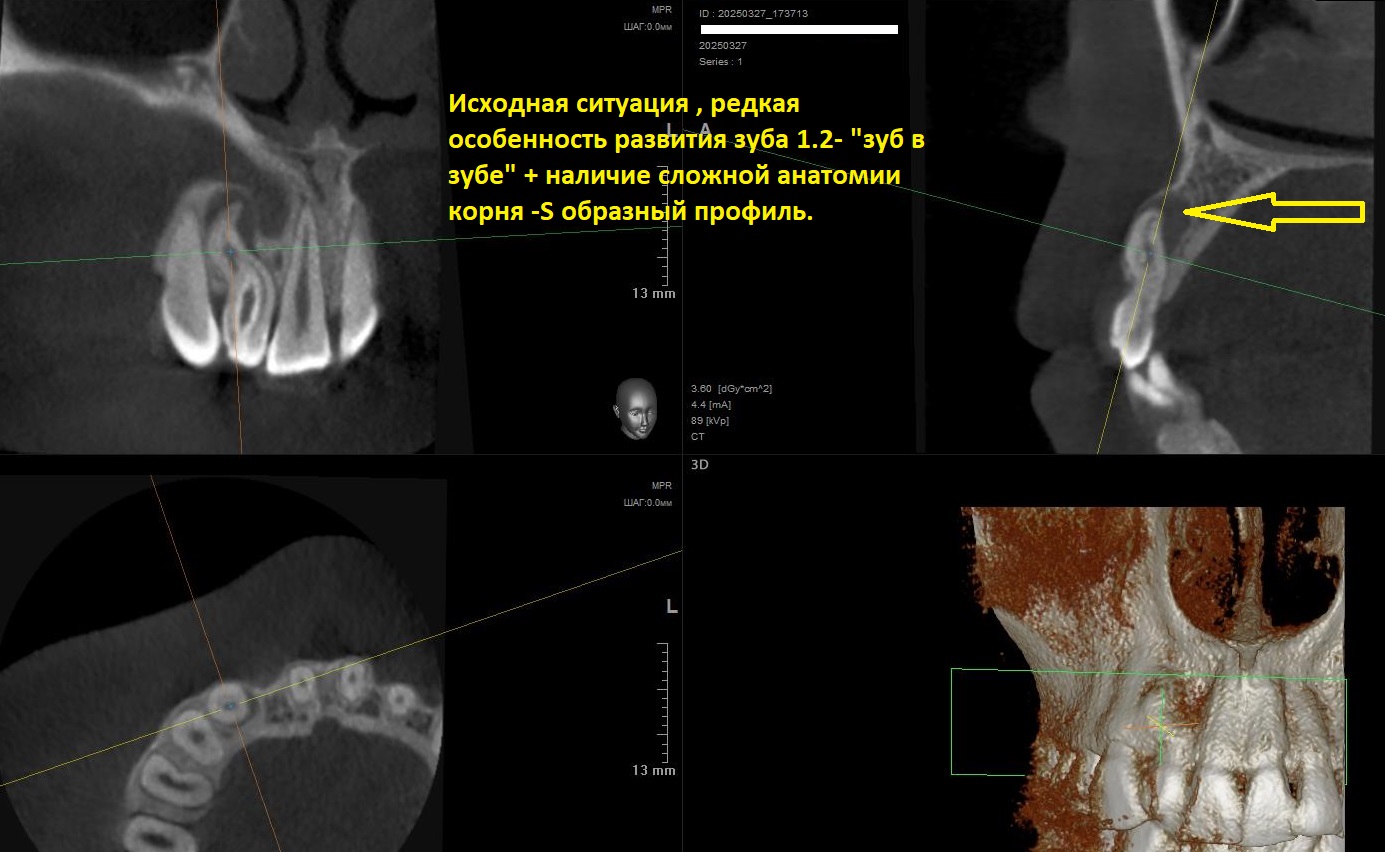

В стоматологию МС обратилась молодая девушка с жалобами на боль в области зуба на верхней челюсти справа.Ранее пациентка обращалась уже в несколько клиник , но после оценки докторами рентгеновского исследования данного зуба предлагался только один неутешительный вердикт- удаление.После оценки 3D рентген исследования зуба стало понятно , что так смущало других докторов.В данном случае в зубе оказалась достаточно редкая особенность развития- Dens invaginatus (зуб в зубе), простыми словами внутри зуба находился еще один маленький недоразвитый зуб, также особую сложность придавал так называемый S образный изгиб корня.